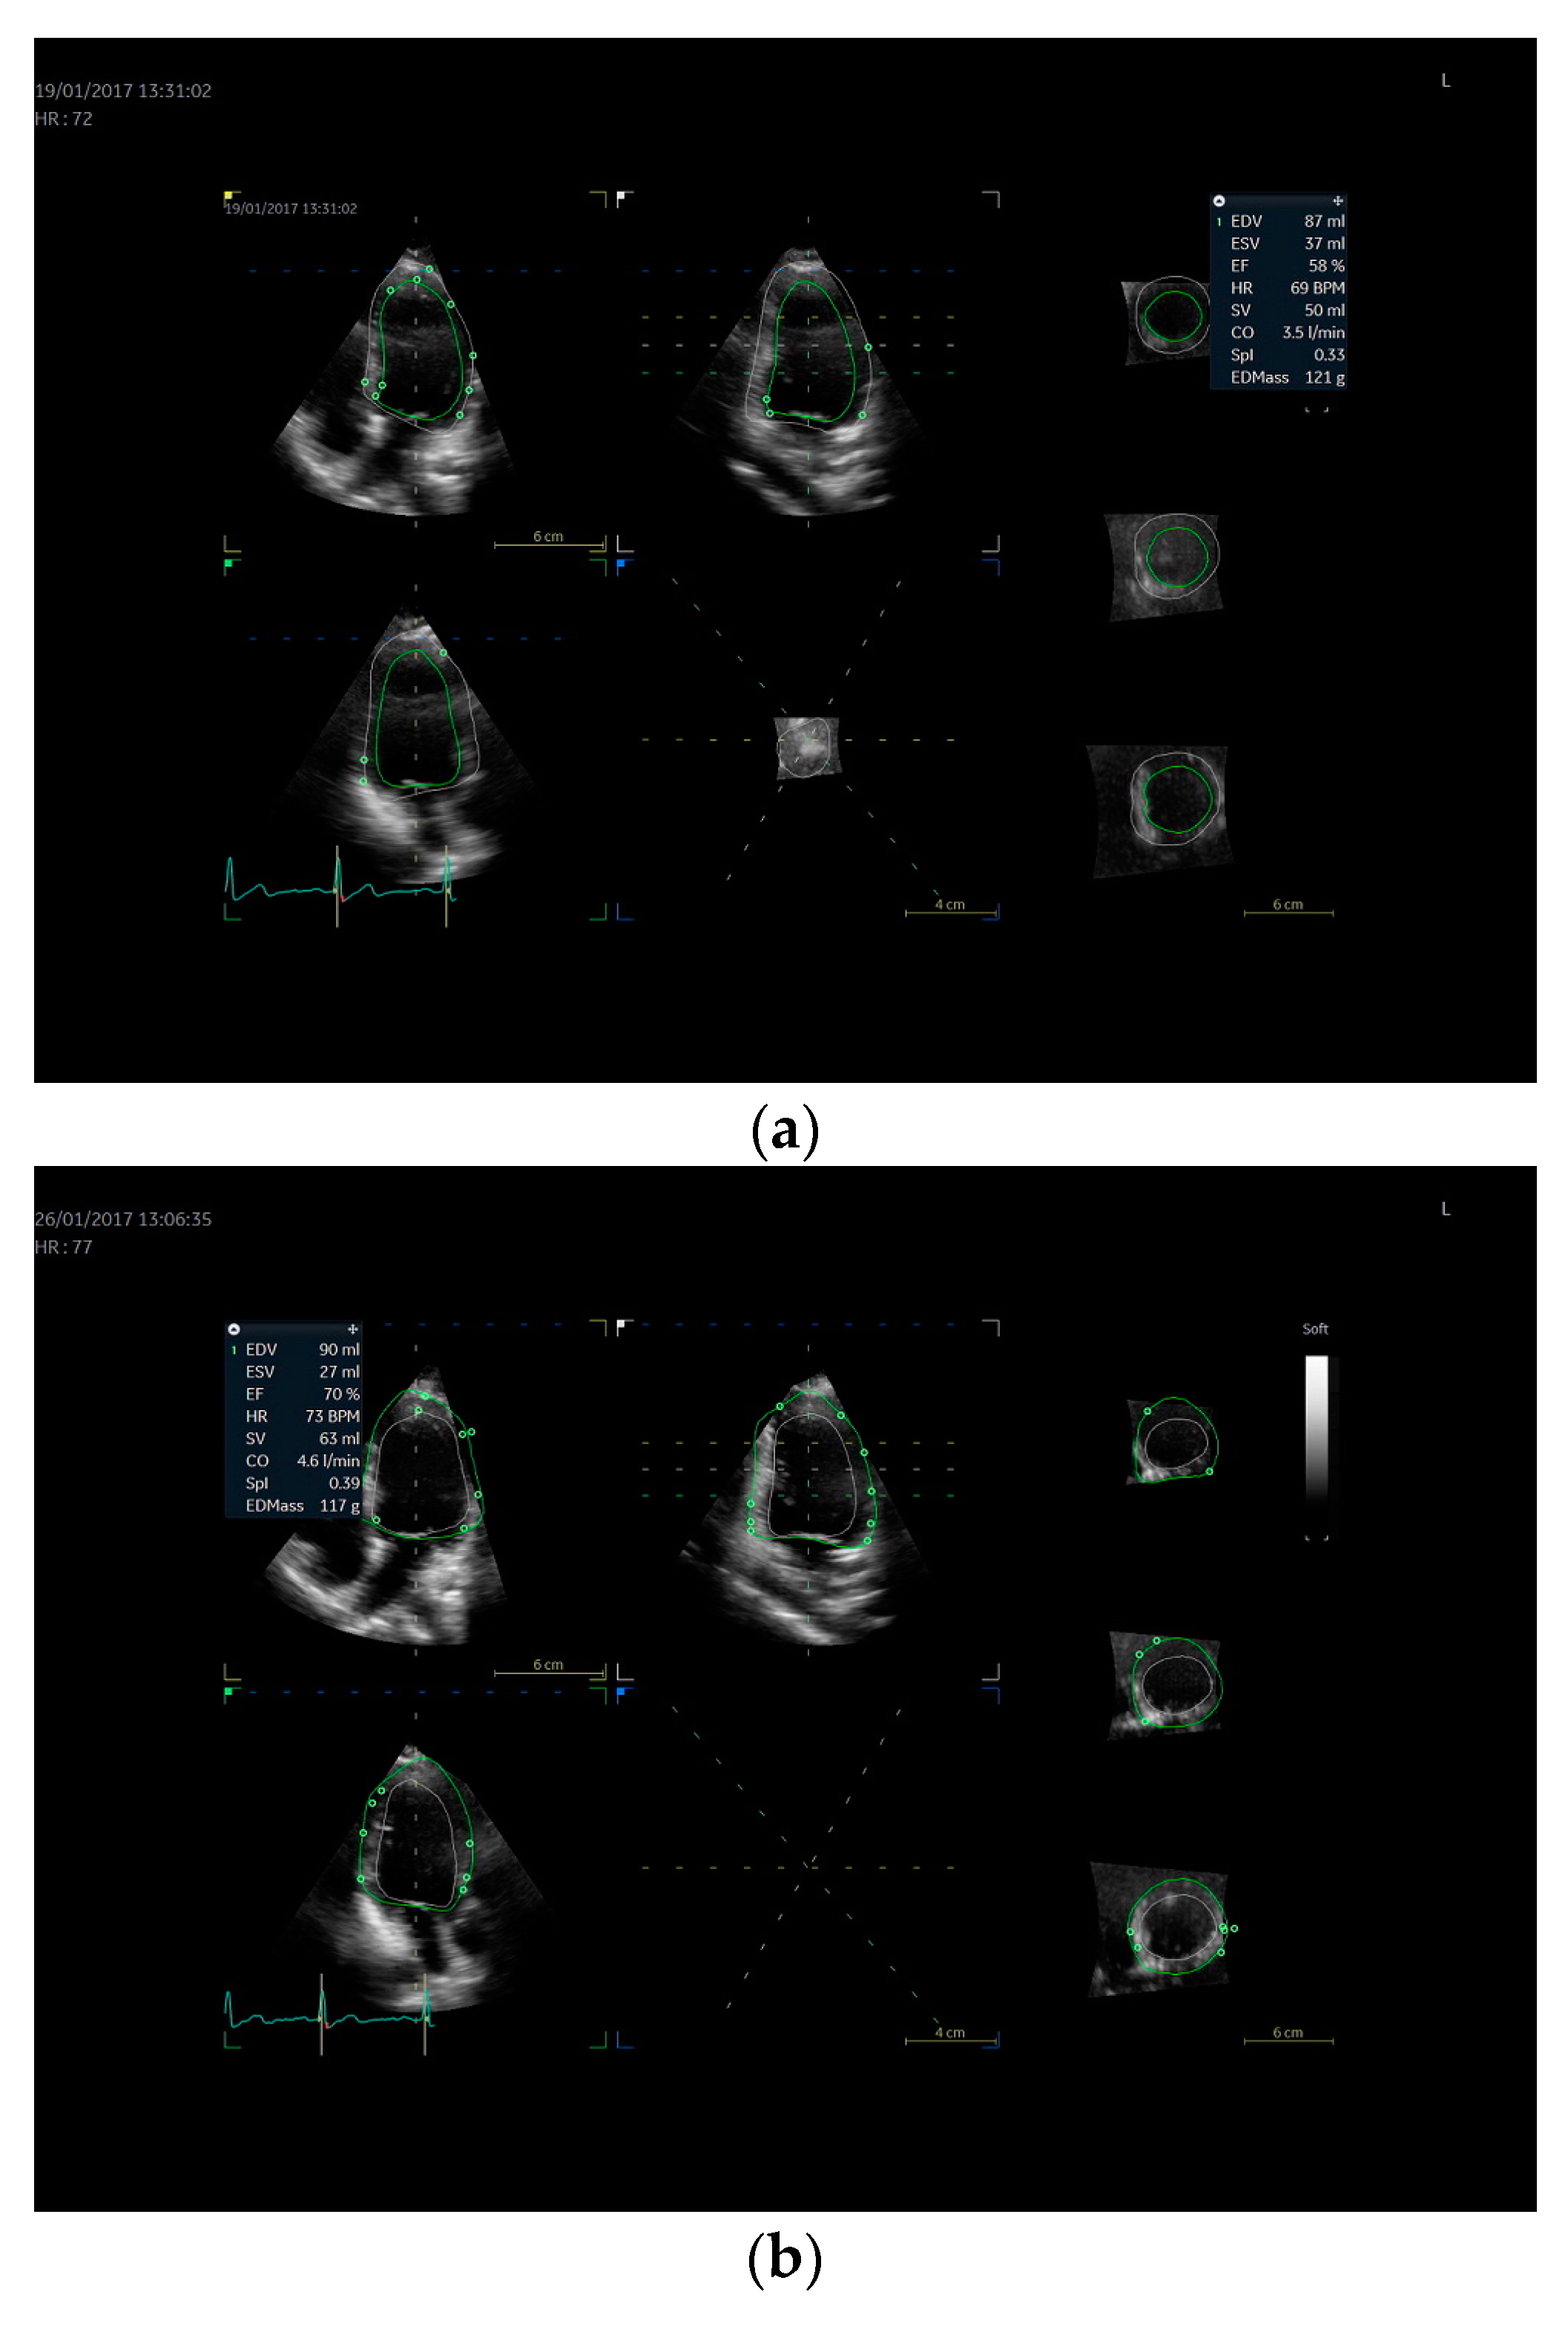

2.4. Echocardiography